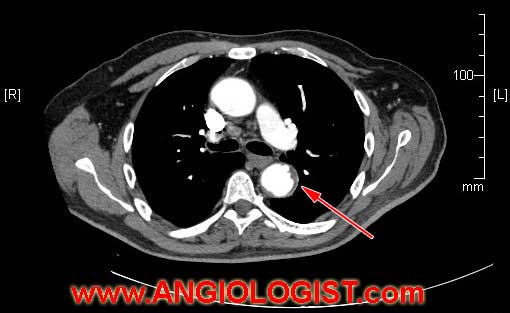

Non-invasive arterial visualization should be utilized. Angio-CT is a preferred choice of imaging study to use for the imaging of arteries and diagnosis of sources of emboli (atherosclerotic plaques or aneurysms).